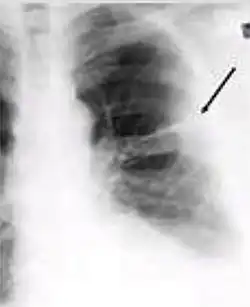

-

Chest X-ray of a person with advanced tuberculosis: Infection in both lungs is marked by white arrow-heads, and the formation of a cavity is marked by black arrows.